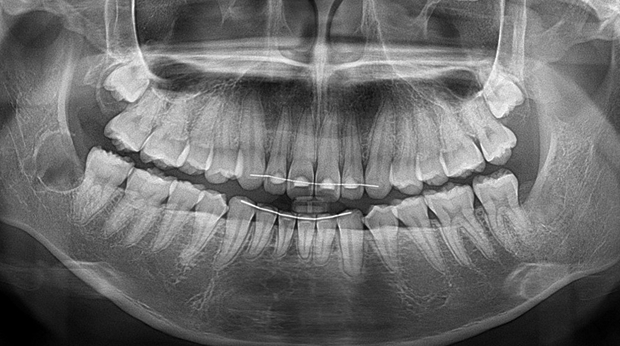

임플란트와 사랑니 발치는 외과적 시술로 잇몸을 절개하는 외과적 시술은

짧으면 짧을 수록 시술 후 붓기와 통증이 최소화됩니다.

치과의사 경력 14년차 구강외과 전문의가 빠르고 안전하게, 아프지 않게 수술해 드립니다.

치과경력 14년차 구강외과 전문의

연세대학교 치과대학 구강외과 임상 조교수